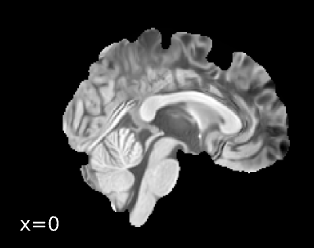

Brain surfaces were reconstructed usingrecon-all[FreeSurfer 7.3.2,

RRID:SCR_001847, @fs_reconall], and the brain mask estimated

previously was refined with a custom variation of the method to reconcile

ANTs-derived and FreeSurfer-derived segmentations of the cortical

gray-matter of Mindboggle [RRID:SCR_002438, @mindboggle].

A T2-weighted image was used to improve pial surface refinement.